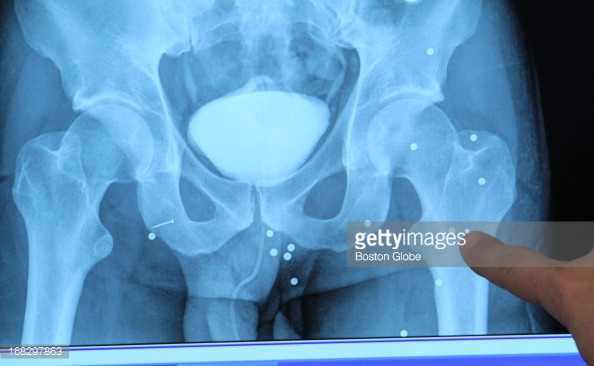

These came into evidence today; it's the BBs and shrapnel still embedded in Marc Fucarile's body. #Tsarnaev

CDTLzOcUMAEaISg.jpg

CDTLzOcUsAA2IsM.jpg

CDTLzOkUsAAopYZ.jpg

Jim Armstrong @JimArmstrongWBZ · Apr 23